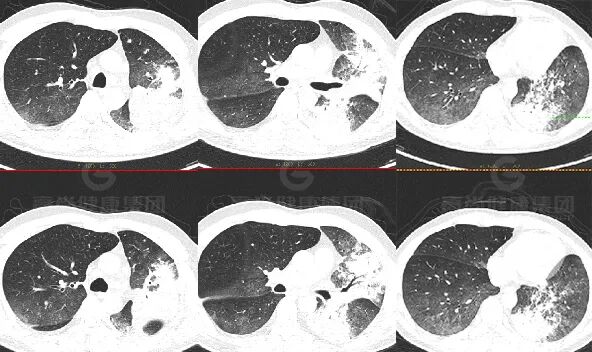

PET/CT 图像

影像特征:

外周分布 (起源外围、由外向内蔓延)

实变和磨玻璃阴影

病理性支气管充气征

实变内有密度较低、强化较低区

「假空洞」/「蜂窝」征

周围小结节,树芽征少

间质增厚

胸膜改变:糊墙征